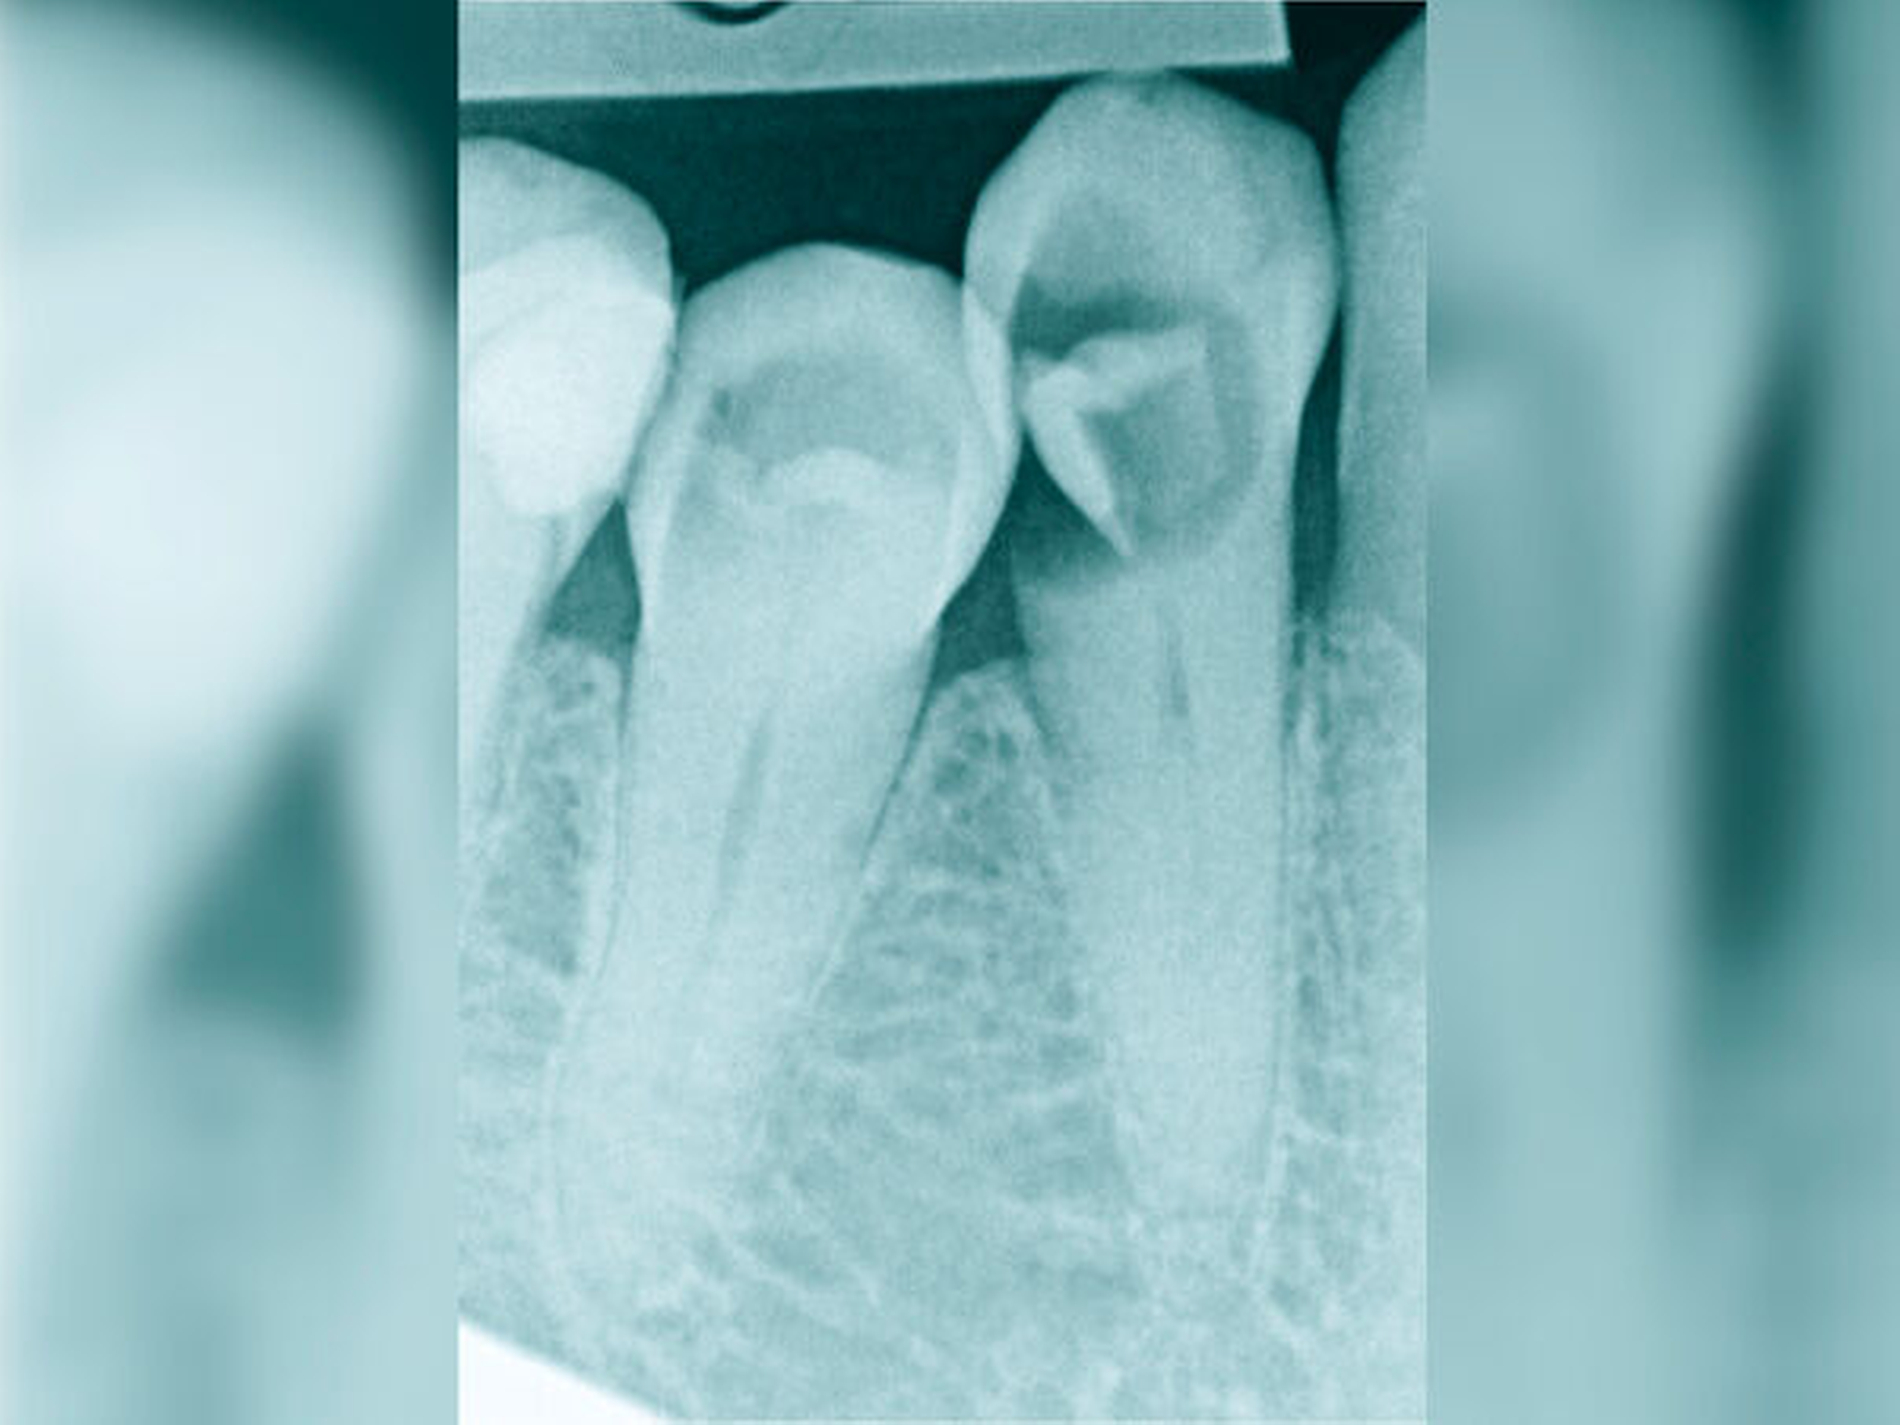

Röntgenbilder können genutzt werden, den anatomischen Schwierigkeitsgrad zu ermitteln. Lässt sich ein Wurzelkanal vollständig bis zum Apex mit einem Krümmungswinkel bis zu 30 Grad und einem großen gleichmäßigen Krümmungsradius erkennen, ist keine erhöhte Schwierigkeit in der Therapie zu erwarten (Abbildungen 1 und 2).

Krümmungsradius: Ist demgegenüber der Verlauf des Wurzelkanals unterbrochen, kann meist mit einer tiefen Wurzelkanalaufteilung gerechnet werden (Abbildung 3) [Reuver, 2002].

Die Schwierigkeit in der Therapie nimmt zu, wenn die Wurzelkanalkrümmung mehr als 30 Grad beträgt, der Krümmungsradius abnimmt (enge Krümmung) oder Mehrfachkrümmungen vorliegen [Duke et al., 2015; Pedulla et al., 2020]. Typisch für Mehrfachkrümmungen sind vor allem mesiale Wurzelkanäle unterer Molaren (Abbildung 4).